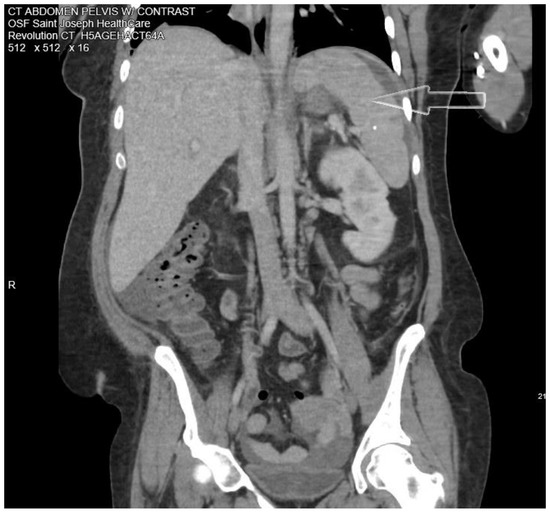

Introduction: The annual incidence of infective endocarditis (IE) is 3–9 cases per 100,000 in developed countries and most cases are due to staphylococci and streptococci. IE due to Gram-positive anaerobic cocci (GPAC) is very rare. Case report: We present a case of a 38-year-old female with Anaerococcus hydrogenalis bacteremia and infective endocarditis of the native mitral valve. She presented with fever, chills, and abdominal pain. A computed tomographic scan of the abdomen showed splenic abscesses. Blood cultures and broad-range PCR from the splenic abscess sample were negative. Transthoracic echocardiography showed a mobile filamentous structure on the atrial side of the anterior mitral leaflet which was suggestive for infective endocarditis. Karius test (cell-free microbial DNA testing) showed Gram-positive anaerobic cocci Anaerococcus hydrogenalis. She was successfully treated with antibiotics. Conclusions: In cases of infection with fastidious organisms like GPACs, the use of next-generation sequencing (NGS) can allow the correct identification of culprit pathogens and streamlined treatment. Full article

Show Figures

Figure 1